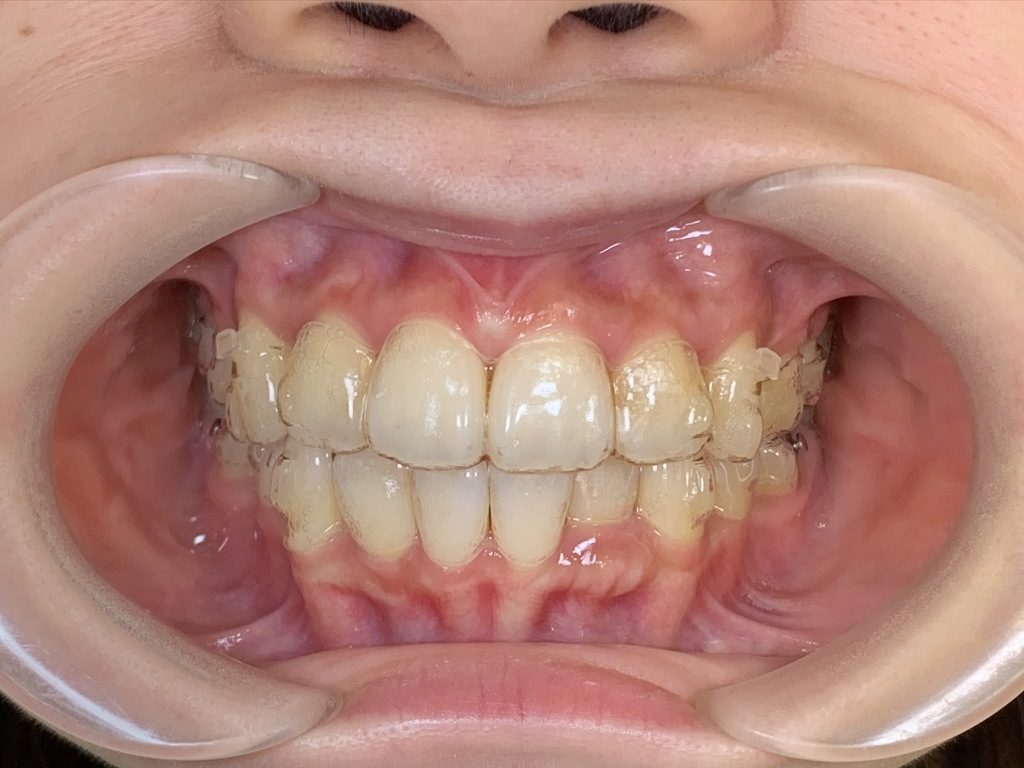

↑全く「浮き」がない状態です。

このようにしっかりとチューイーを毎回使用し、全ての部位を「浮き」がなくマウスピースをフィットさせることが重要です☆